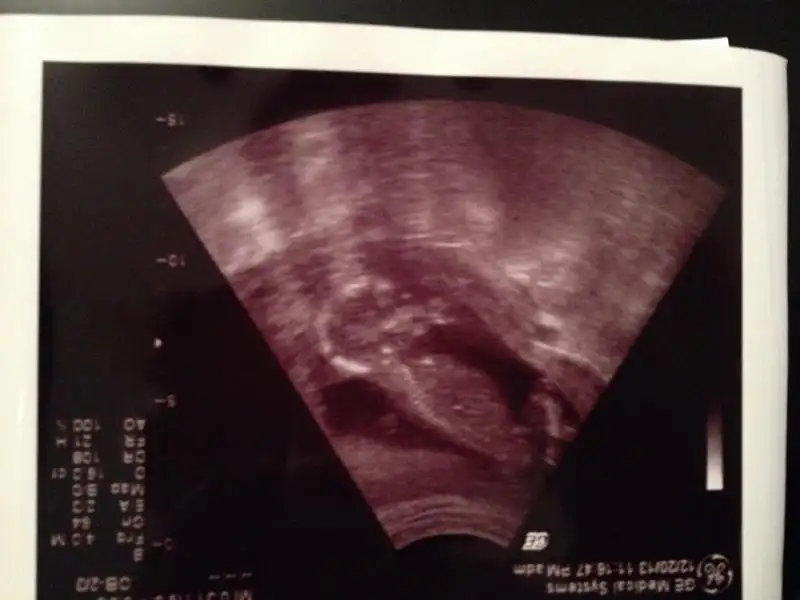

zeynep 341 de yeni foto yükledim bunlara da bakar mısın yorum yapan arkadaşlar erkek dediler ama nedense hala kızdan yana umudum var yeşerip yeşerip duruyor gönlümden böyle geçtiği için mi acaba elbette her zaman hayırlısını diliyorum

bir daha bakıp yorumlar mısın lütfen

Ayni bu goruntu benim suanki kizimin ultrasonuna benziyor canim bendede bu haftada kesin erkek demusti sonrada kiz dedi Bence senin bebis de kiz olucak kesin haber ver sonucunu

Benim ultrasonla ayni yeni koydugun kizin olucak insallh